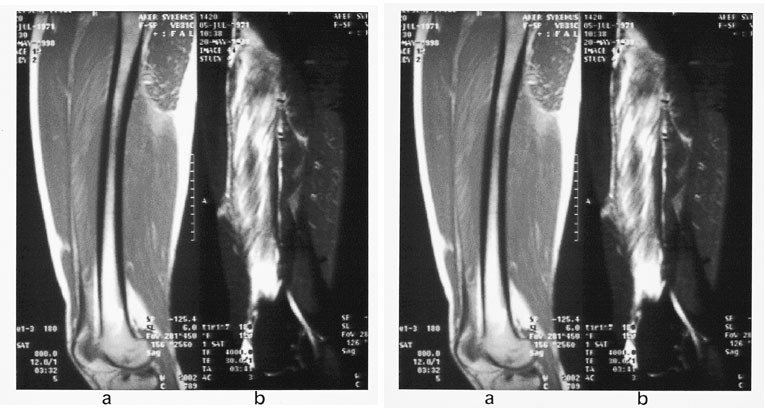

Akutt muskelskade kan være forårsaket enten av direkte penetrerende kraft, som gir en laserasjon, eller av stump kraft, som gir kontusjon (fig 18). Det er sjelden pasienter med laserasjon kommer til MR i den akutte fase. Eventuell senkomplikasjon med fettdegenerasjon kan identifiseres som nedsatt muskelmasse og høysignal på T1-vektet sekvens. Ved muskelkontusjoner vil ofte T1-vektet sekvens være normal, mens STIR-sekvensen viser økt signal i muskelen.

Lange og trettende muskeløvelser kan gi et klinisk bilde med muskelsmerte, udefinerbar sårhetsfølelse, hevelse og stive ledd i timer og dager etterpå. Dette er kjent som DOMS (delayed onset muscle soreness) i engelsk litteratur. Det kliniske bildet kan vare opptil en uke. MR-funnet likner forandringene man ser ved mild grad av muskelkontusjon og kan være positivt i flere måneder (fig 19). Ved gjentatte øvelser kan man se forandringer ved muskel-sene-overgangen, forenlig med såkalt kronisk muskeloverforbrukssyndrom.